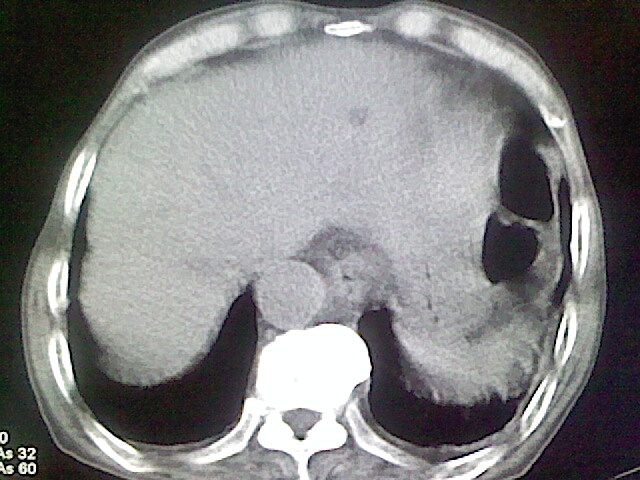

以下是引用zsl6918在2008-8-28 16:49:00的发言:[br]双肺炎性病灶,食管狭窄估计与心房增大压迫所致。

以下是引用xulianj在2008-8-28 20:36:00的发言:[br]慢支肺气肿伴感染,右上肺陈旧性结核;食道建议胃镜检查。

以下是引用wqs571018在2008-8-28 21:18:00的发言:[br]慢支继发感染,右上肺陈旧性结核;食道建议胃镜检查。